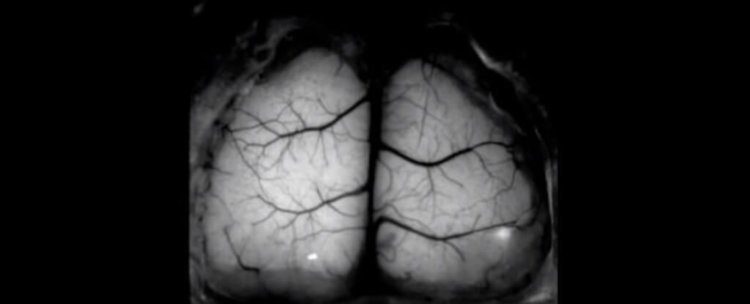

После этого грызунам провели хирургическую операцию, в ходе которой была удалена верхняя часть настоящего черепа мышей. Ее ученые заменили прозрачным имплантатом. Такая манипуляция позволила исследователям наблюдать за мозговой активностью животных и получать изображения всего органа в режиме реального времени.